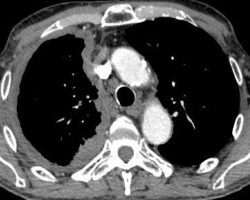

Thrombose de l’aorte